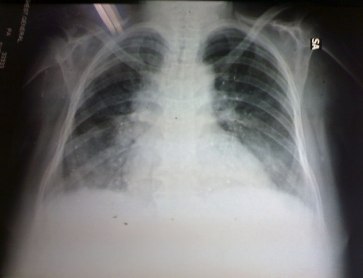

Case 23

She is in

her fifties and was perfectly fine until 4 months ago when she began

suffering from gradual progressive dyspnea, fever and in spite of many

medical consultations and treatments her condition continued to get

worse so that attended us.

Examination:

There was marked pallor, tachycardia,

tachypnea (50 c/m), systolic murmur, harsh vesicular breathing.

Chest X-ray: see the photo.